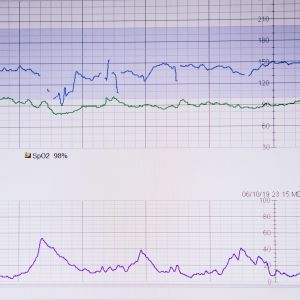

Cardiologie

Cardiologie